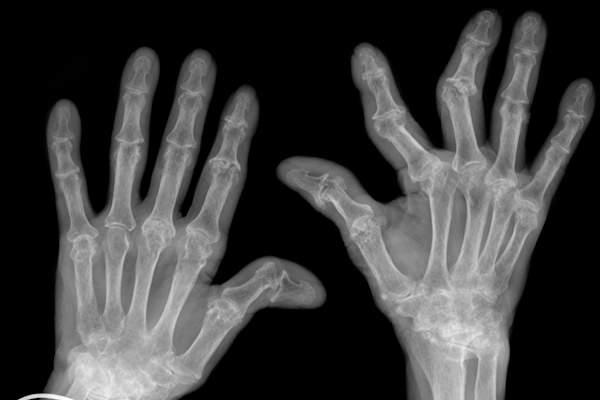

依靠影像学检查

你的风湿病可以得到RA如何被诊断获得基线图像,然后用新的定期扫描跟踪,根据需要影响你的关节更好的感觉。“你可以期待你的手,手腕和脚部的X光片,”巴特博士说。“如果你的关节都肿了,我们可以挖掘的地方进行测试的液体。”一些医生订购更多敏感成像测试,像CT扫描,超声波或核磁共振,但这是不常见的。“这是需要核磁共振成像的患者不在少数,” Ludmer博士说。